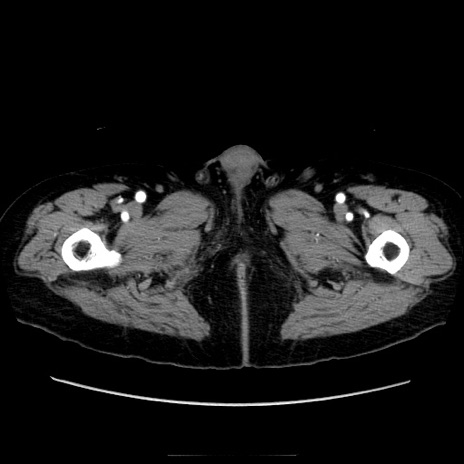

冠状断像